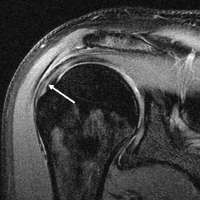

MRI

Magnetic resonance imaging (MRI) and ultrasound[27] are comparable in efficacy and helpful in diagnosis although both have a false positive rate of 15 - 20%.[28] MRI can reliably detect most full-thickness tears although very small pinpoint tears may be missed. In such situations, an MRI combined with an injection of contrast material, an MR-arthrogram, may help to confirm the diagnosis. It should be realized that a normal MRI cannot fully rule out a small tear (a false negative) while partial-thickness tears are not as reliably detected.[29] While MRI is sensitive in identifying tendon degeneration (tendinopathy), it may not reliably distinguish between a degenerative tendon and a partially torn tendon. Again, magnetic resonance arthrography can improve the differentiation.[29] An overall sensitivity of 91% (9% false negative rate) has been reported indicating that magnetic resonance arthrography is reliable in the detection of partial-thickness rotator cuff tears.[29] However, its routine use is not advised, since it involves entering the joint with a needle with potential risk of infection. Consequently, the test is reserved for cases in which the diagnosis remains unclear.

Diagnostic modalities, dependent on circumstances, include X-ray, MRI, MR arthrography, double-contrast arthrography, and ultrasound. Although MR arthrography is currently considered the gold standard, ultrasound may be most cost-effective.[16] Usually, a tear will be undetected by X-ray, although bone spurs, which can impinge upon the rotator cuff tendons, may be visible.[17] Such spurs suggest chronic severe rotator cuff disease. Double-contrast arthrography involves injecting contrast dye into the shoulder joint to detect leakage out of the injured rotator cuff[18] and its value is influenced by the experience of the operator. The most common diagnostic tool is magnetic resonance imaging (MRI), which can sometimes indicate the size of the tear, as well as its location within the tendon. Furthermore, MRI enables the detection or exclusion of complete rotator cuff tears with reasonable accuracy and is also suitable to diagnose other pathologies of the shoulder joint.[19]